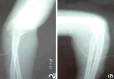

Case report: A 19-year-old male with a history of pain, swelling, and restriction of movements of the right elbow for the last 6 years with a history of difficulty in eating and combing hair with the right hand. History of trauma to his right elbow 6 years ago for which he underwent conservative native treatment with massage. Physical examination found a swelling over the right medial elbow joint of size approximately 7 cm × 6 cm × 3 cm, with no local rise of temperature or tenderness. There was a fixed flexion deformity of 75°. There were no sensory or vascular deficits. Under general anesthesia, through the anterior approach, an irregular bony mass was visualized which was excised. Through a posterior approach, a skin incision was made, subcutaneous tissue dissected, muscles retracted and then a calcified mass visualized over the olecranon process which was excised. The post-operative period was uneventful. Elbow joint mobilization was started from day 2 which showed significant correction of fixed flexion deformity.